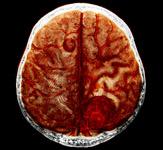

Brainsuite iCT integrates intraoperative CT scans with surgical planning and ceiling-mounted navigation. Automatic Image Registration uses the latest intraoperative images to ensure fast and sterile patient registration for uninterrupted navigation back at original accuracy. Up-to-date images combined with navigation provide surgeons with immediate quality control and the ability to check their progress before concluding surgery. Intraoperative CT is considered to be a versatile tool for multiple surgical specialties. Because the scanner can be used for surgical and diagnostic imaging, it is considered a financially feasible solution for hospitals worldwide.

The 16-slice Aquilion LB features the industry’s largest gantry aperture of 90 cm and the industry's largest scan field of 70 cm, covering more anatomy.

The unique 70 cm scan field, up to 40 percent greater than other large-bore CT systems, delivers detailed image quality and reduces hidden anatomical areas for diagnoses, simulation and planning. The Aquilion LB delivers a field-of-view of 70 cm without requiring extrapolation algorithms through Toshiba's Quantum Detector technology.